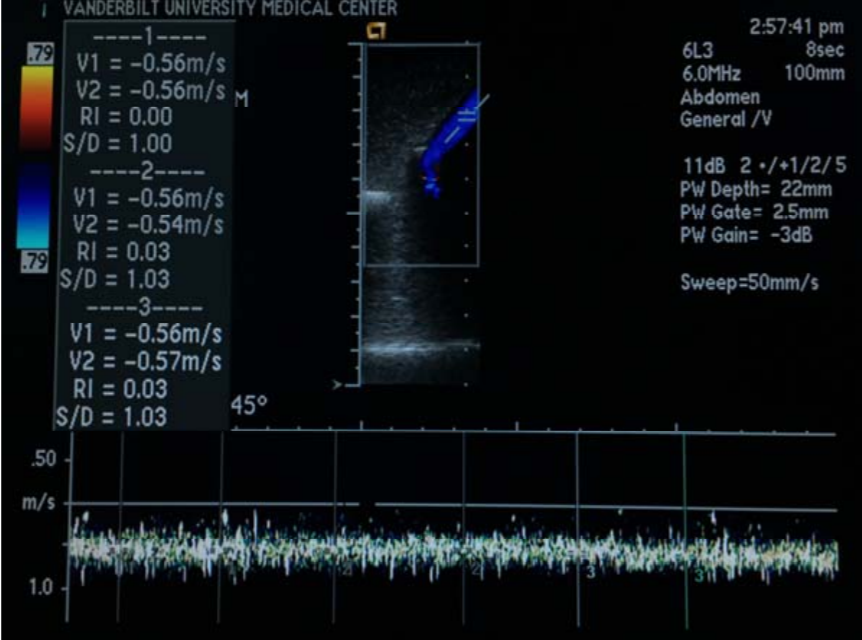

• Executed an NDA with a leading ultrasound company for an ultrasound probe arm developed by Raj Gupta from the Department of Anesthesiology